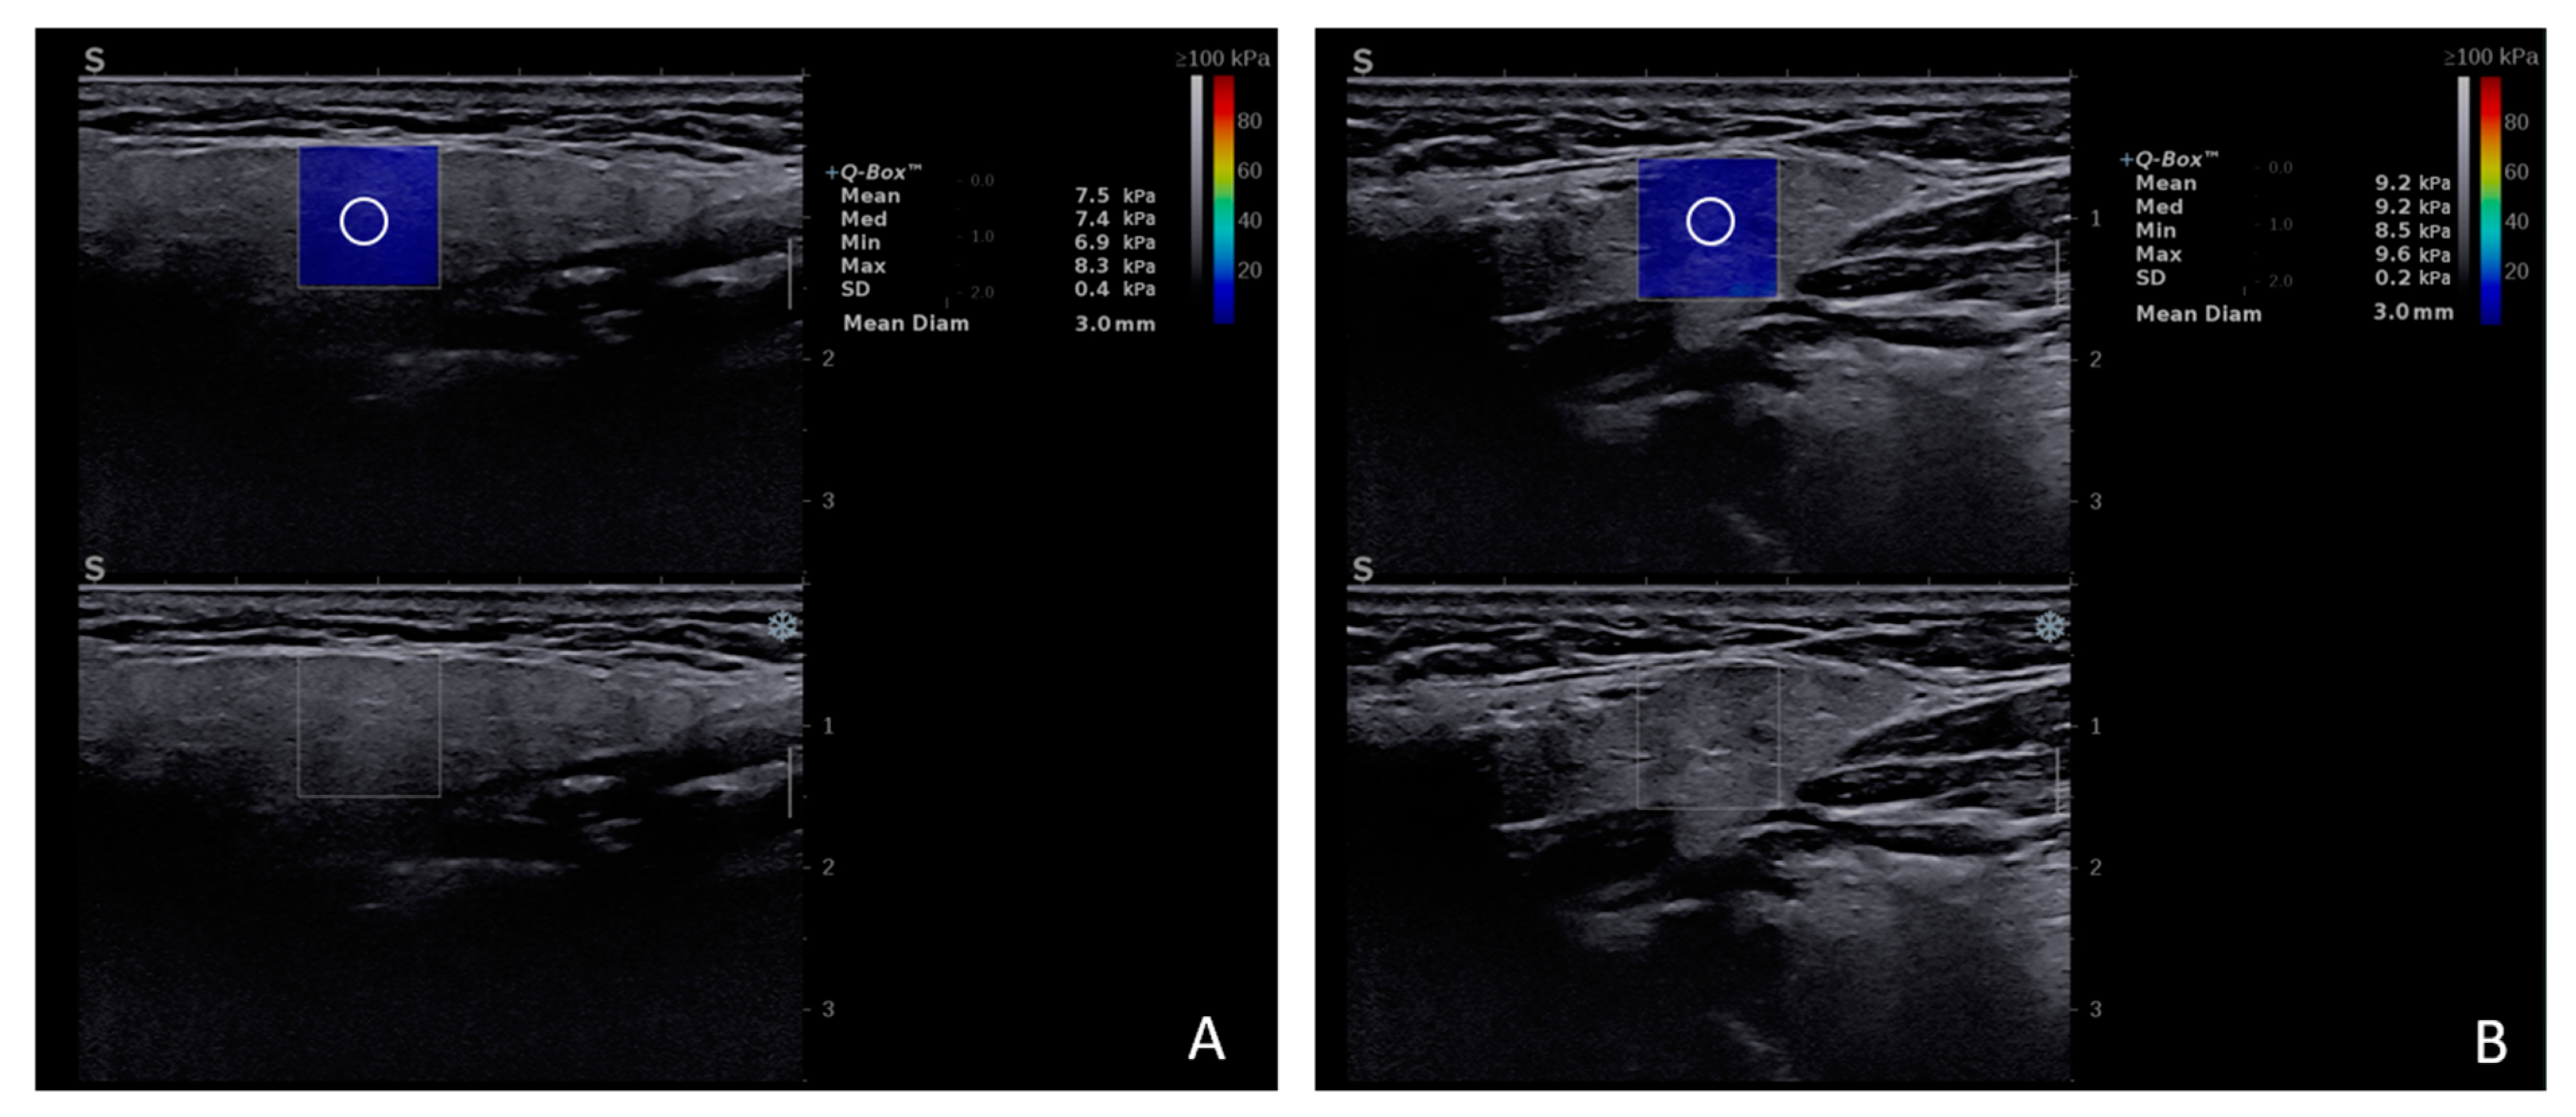

The normal stiffness values as determined by 2D-SWE (Figure 2) range within 5.46–9 kPa for the parotid gland (PG) and 8.63–11 kPa for the submandibular gland (SMG). Age, gender, and body mass index were not found to be significant confounding factors to the elasticity modulus of MSG [15,16]. No statistically significant differences were detected between the SWE velocity values of the MSG of smoker and non-smoker healthy subjects [17].

Figure 2.

2D-SWE examination of the parotid gland (A) and submandibular gland (B) healthy subject.